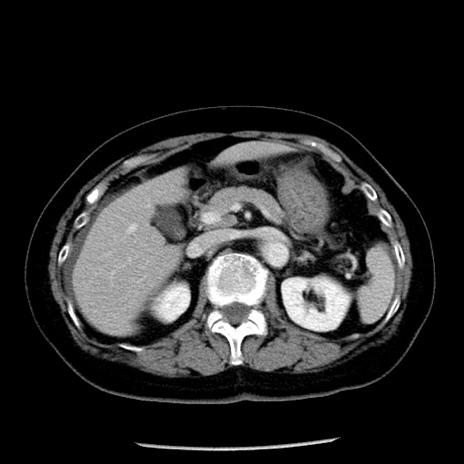

症例13(横断像)

【症例】70歳代女性

【主訴】腹痛、嘔吐

【現病歴】15時間程前(昨晩)より腹痛あり。今朝になっても症状の改善なく、嘔吐あり。腹痛も増悪あり、救急外来受診。

【既往歴】子宮癌全摘術後

【身体所見】意識清明、BP 121/72mmHg、P 74bpm、SpO2 100%(RA)、腹部:平坦・軟、腸雑音ほぼ聴取せず。下腹部・心窩部・臍左上に圧痛あり。反跳痛なし。

【データ】WBC 10600、CRP 0.15